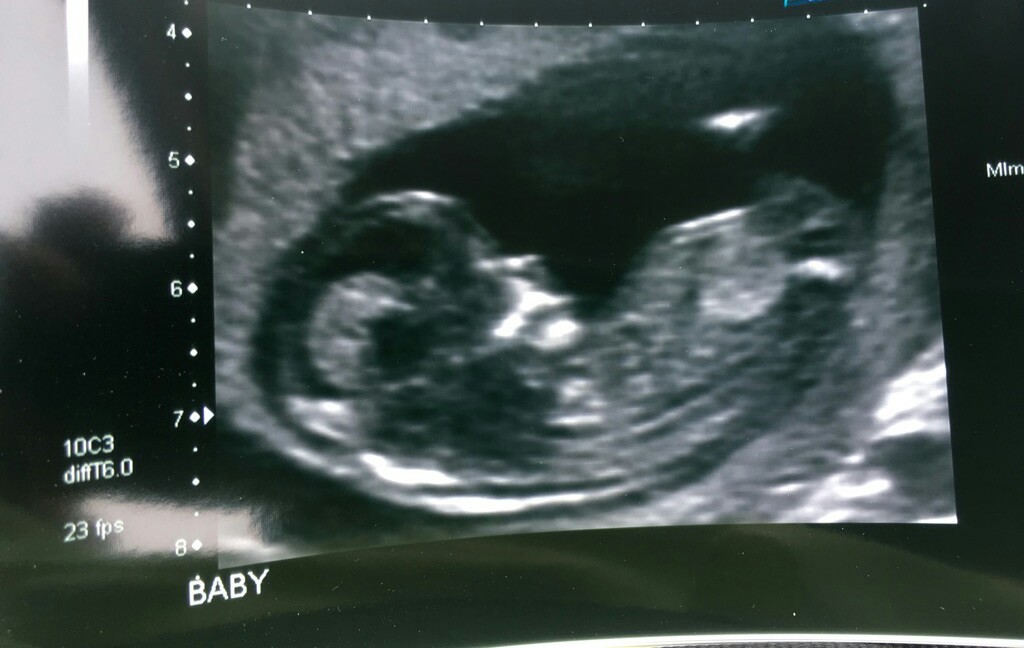

Attachment 39166Attachment 39167Attachment 39168 Can anyone see a male or female nub in these pics?

Cute baby! Nub isn’t imaged though. Anymore pics!

I don't see a nub, sorry.